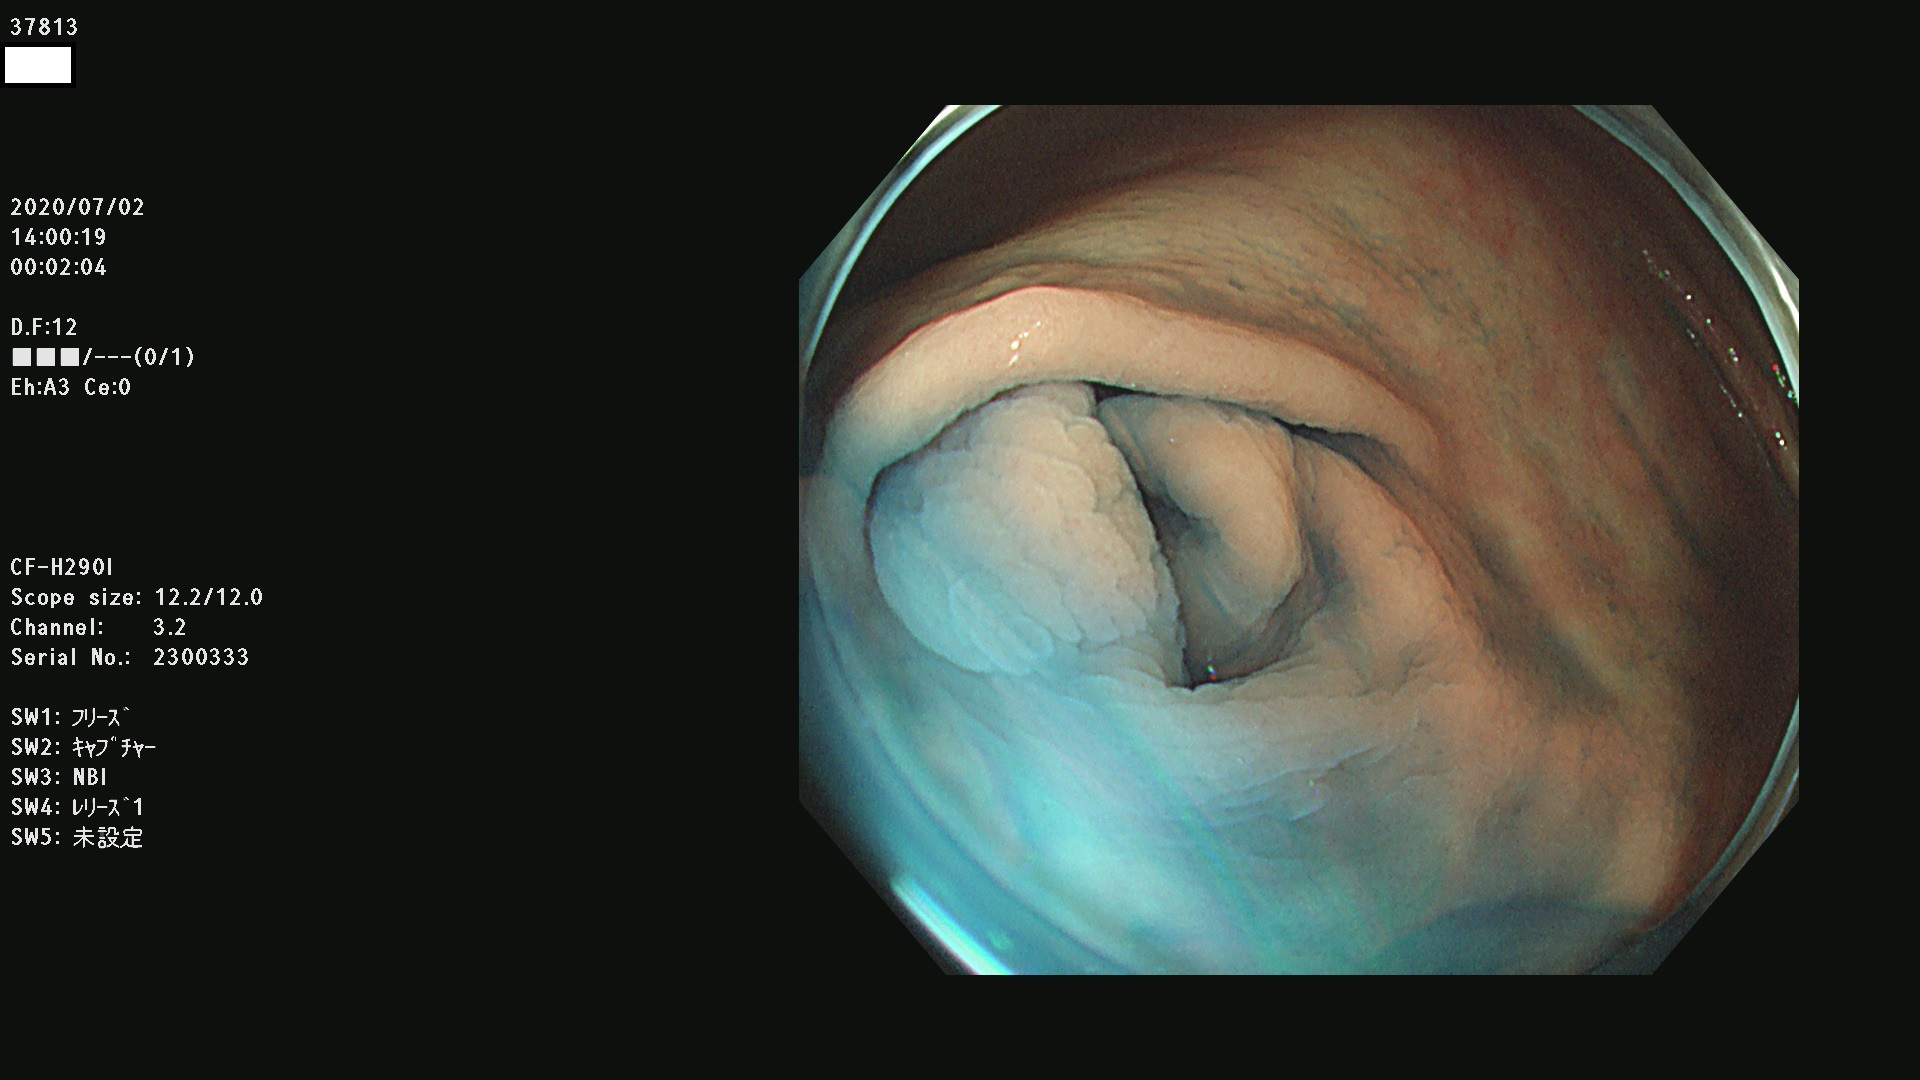

腺腫発見率 75 % (カルテ番号 37800〜37899の100名の方の検査結果で集計)大腸癌検診最新情報

以下のカルテ番号の方に腺腫(Adenoma,Group3〜5)が見つかりました(集計法)

37800(SSAPのみ) 37801 37802 37803 37804 37805 37806 37807 37808 37809(SSAPのみ) 37810 37811 37812 37813 37814 37815 37817 37818 37819 37820 37821 37822 37824 37825 37826 37827 37828 37829 37832 37833 37836 37837(SSAPのみ) 37839 37840 37842 37844 37845(SSAPのみ) 37847 37849 37850 37851 37852 37853(SSAPのみ) 37855 37856 37857 37860 37861 37862 37863 37864 37867 37868 37871 37874 37876 37877 37879 37880 37881 37882 37883 37886 37887 37888 37889 37890 37891 37892 37893 37894 37896 37897 37898 37899

発見困難で危険性の高い平坦型病変(上記100名より抽出) ![]()